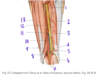

Which structure is labeled by #12?

Function?

Innervation?

Vastus lateralis

Knee extension (inserts on greater trochanter of femur)

Femoral nerve

Which structure is labeled by #9?

Semimembranosus

Which structure is labeled by #10?

What is its function?

What are its attachments?

Tibialis posterior

Foot inversion, plantarflexion

Tibia, fibula, interosseous membrane + sole of the foot (tarsals)

Which structure is labeled by #5?

Tibial nerve